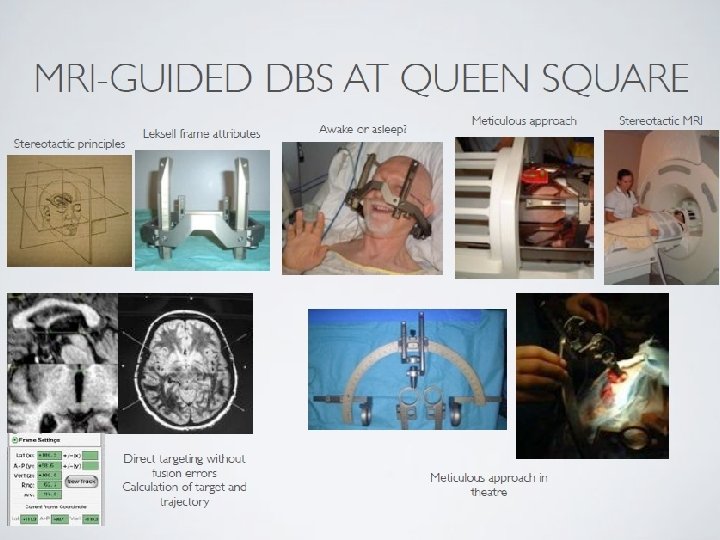

Neuromodulation for chronic intractable primary headache Laurence Watkins Victor Horsley Department of Neurosurgery National Hospital for Neurology & Neurosurgery BASH Hull January 2011